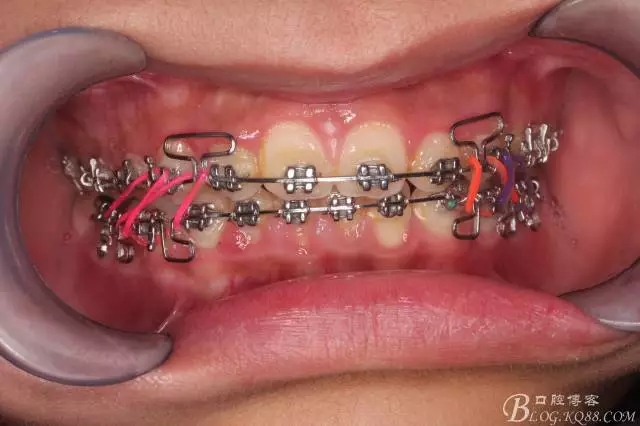

看看口內(nèi)照吧!真象“大暴牙”v假象“大暴牙”

三度深覆合,三度深覆蓋,尖牙,磨牙均二類關(guān)系!